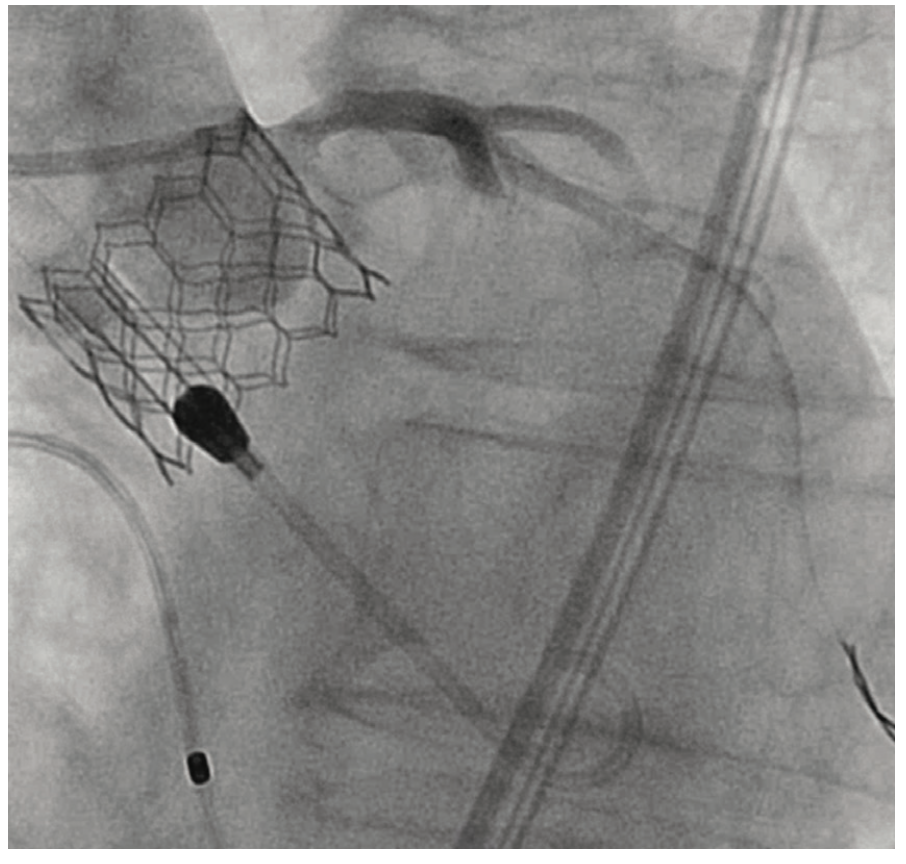

An 81-year-old female with symptomatic severe aortic stenosis, logistic EuroSCORE I (European System for Cardiac Operative Risk Evaluation) of 14.46%, EuroSCORE II of 3.44%, and Society of Thoracic Surgeons (STS) estimated surgical mortality of 3.371%, underwent TAVR. Transthoracic echocardiogram (TTE) showed a heavily calcified aortic valve with a mean gradient of 68 mmHg, aortic valve maximum velocity (Vmax) of 4.2 m/sec, calculated aortic valve area of 0.8 cm2, and normal left ventricular systolic function. Computed tomography angiography (CTA) demonstrated heavily calcified aortic root, leaflets, and annulus. Transfemoral implantation of a 23 mm Sapien 3 (Edwards Lifesciences) valve was performed (Figures 1-2). Using a 20 mm balloon for pre-dilation, the valve was implanted successfully in a 50-50 position (Figure 3). The immediate post-deployment aortogram showed leakage of dye outside the left sinus with no evidence of cardiac tamponade. Despite that fact, the patient developed immediate hemodynamic collapse. QRS widening and ST-elevation were visible on the monitor. Narrowing of the left main coronary artery (LMCA) with reduced TIMI flow (0-1) was evident in angiographic images (Figures 4-5). The patient had a cardiac arrest, cardiopulmonary resuscitation was initiated, and she went into cardiogenic shock. The patient stabilized with the placement of venoarterial extracorporeal membrane oxygenation (VA-ECMO) and the insertion of the Impella device (Abiomed) (Figure 6). An emergent percutaneous intervention was performed within minutes from collapse by the deployment of two drug-eluting stents from the LMCA into the left anterior descending (LAD) coronary artery (Figure 7) using the Culotte technique with final kissing-balloon dilatation. After the restoration of coronary flow, the patient was admitted to the cardiothoracic intensive care unit. She remained stable. The ECMO and Impella implant was removed after 7 days. Postprocedure on day 14, the patient was discharged to a rehabilitation facility. Echocardiography showed a well-functioning valve with acceptable residual gradient and mild to moderate paravalvular leak.